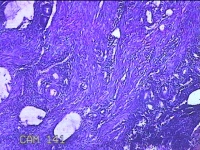

宫腔内容物

性别

女

年龄

45岁

临床诊断

子宫内膜息肉

一般病史

宫腔异常回声3月。

标本名称

大体所见

灰白暗红色不规则碎组织3x2x0.8cm一堆。

图2